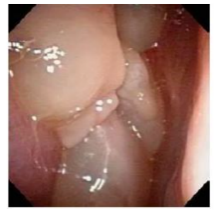

多発する鼻ポリープ

好酸球(こうさんきゅう)という体の中の炎症に関わる細胞が鼻や副鼻腔(鼻の奥にある空洞)にたまり、強い炎症を起こす病気です。国が指定する、『指定難病』となり、難治性で再発しやすい疾患です。